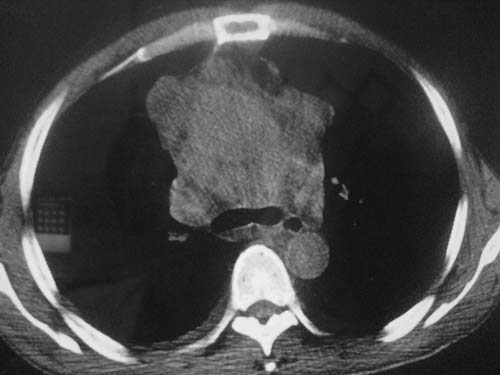

以下是引用科室第一人在2010-3-25 20:30:00的发言:[br]1:纵膈肿瘤性病变,恶性胸腺瘤可能性大伴纵膈右肺门淋巴结转移,右侧胸腔积液。[br]2:右侧肺门肿瘤性病变,纵膈淋巴结转移,右侧胸腔积液。右下叶转移。

以下是引用子期在2010-3-25 21:00:00的发言:[br]先考虑右中央型肺癌伴转移。

以下是引用江广1996在2010-3-25 22:49:00的发言:[br]通常肺癌向纵隔转移多见,纵隔肿瘤向肺内转移少见(有的表现为向肺内侵润)。本例以一元论考虑:右中心型肺癌并纵隔淋巴等多处转移。[br][br][本贴已被 江广1996 于 2010-3-25 22:50:07 修改过]

以下是引用yangyudong333在2010-3-26 6:43:00的发言:[br]“冰冻纵膈”,考虑纵膈淋巴瘤伴肺内及胸膜侵润。